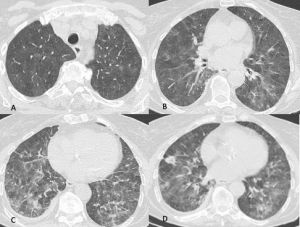

L’agente patogeno più comune è il virus dell’influenza e i segni e i sintomi clinici come anche i reperti di imaging variano a seconda dello stato immunitario dell’ospite. I pattern in TCAR sono molteplici: “vetro smerigliato” e consolidazione; sfumati noduli e micronoduli centrolobulari alcuni con aspetto ad “albero in fiore”; ispessimento dei setti inter ed intralobulari ed ispessimento delle pareti bronchiali (Figura 2). Ingrandimento dei linfonodi mediastinici e versamento pleurico possono essere presenti, sono invece reperti rari nella polmonite da COVID-19.

Figura 2: Uomo di 41 anni con infezione da virus dell’Influenza A, giunge al Pronto Soccorso con febbre, tosse, malessere e lieve dispnea. La TCAR eseguita all’ingresso mostra nelle scansioni assiali (A-B) e nella ricostruzione MPR coronale (C) la presenza di sfumati micronoduli centrolobulari nel lobo superiore destro e nel lobo medio e di aree di aumentata densità con aspetto in parte a "vetro smerigliato" ed in parte consolidativo nel lobo inferiore destro.

Figura 3: Uomo di 65 immunocompromesso affetto da polmonite da Citomegalovirus. Le immagini TCAR assiali (A-B-C) e la ricostruzione MPR coronale (D) mostrano il tipico pattern caratterizzato dalle presenza di "vetro smerigliato" diffuso in entrambi i polmoni con distribuzione simmetrica, si associa la presenza di alcune aree di aumentata densità con aspetto consolidativo in entrambi i lobi inferiori.